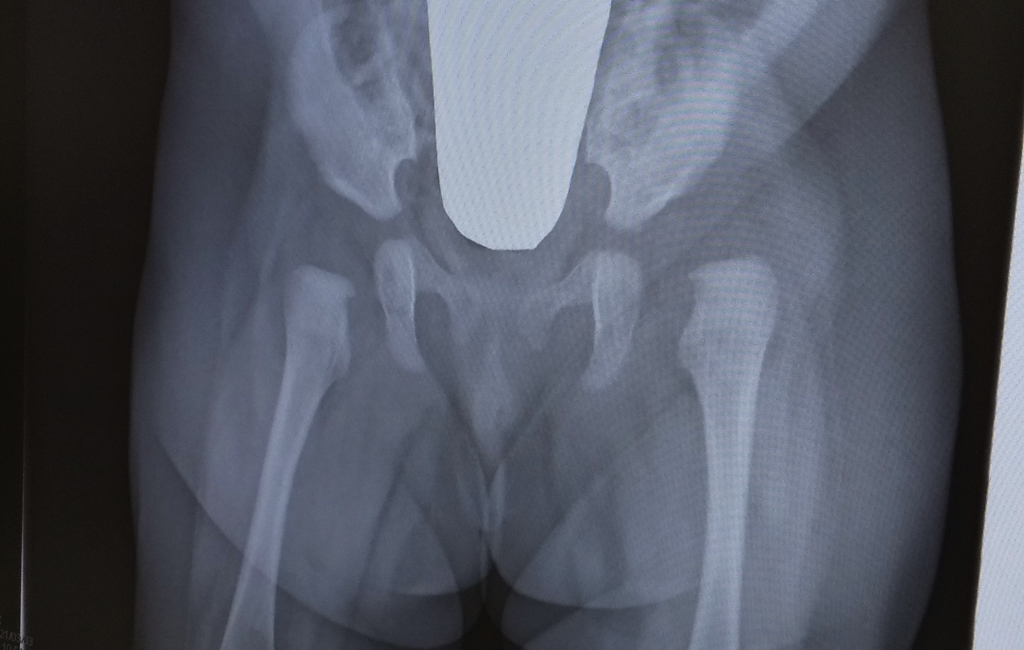

先天性股関節脱臼について